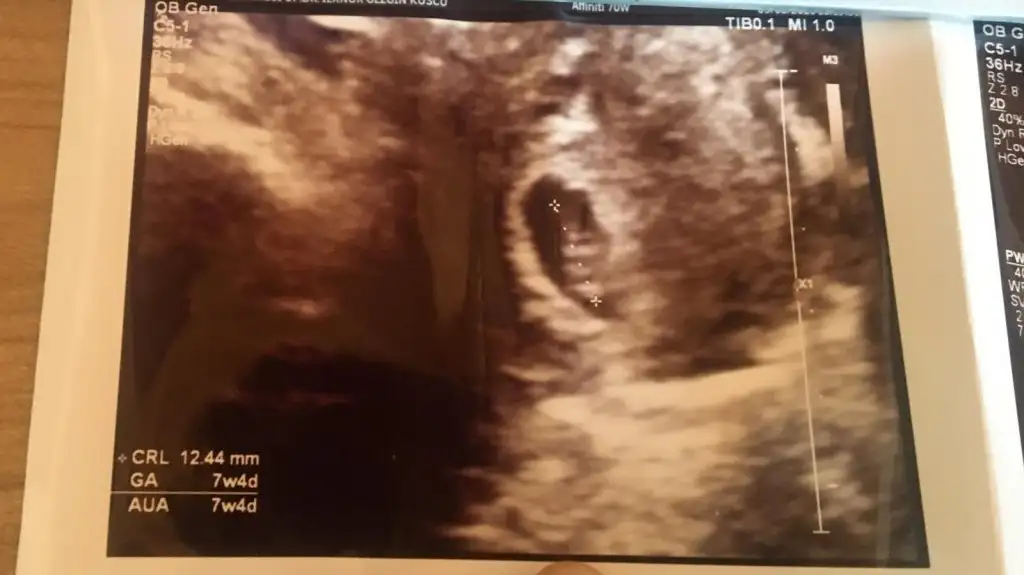

Buna göre erkek en iyi 11 12 13 haftlarIkra meyra Tahminde bulunur musun rica etsem. Karından 7 haftalık ..

Oylemi hayırlısı olsun insallah .Ozaman da paylaşırım tabi. Daha 8 haftalıkBuna göre erkek en iyi 11 12 13 haftlar

Evet erkek görünüyor siz yinede 12-13 olursa tekrar usg paylaşın